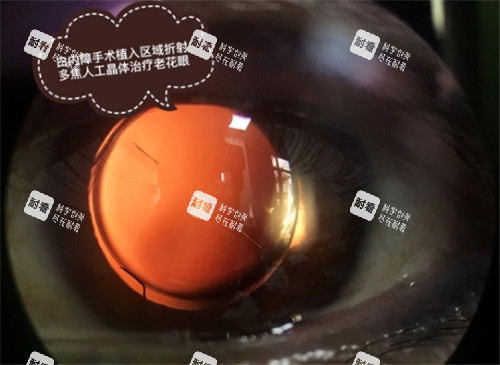

A:政策通常会减免或提供一款指定的、功能基础的人工晶体。如果想选择更高端别的(如非球面、散光矫正型、多焦点晶体等),超出减免范围的部分可能需要个人承担。具体能选哪些,费用如何,一定要在手术前和医生沟通清楚。